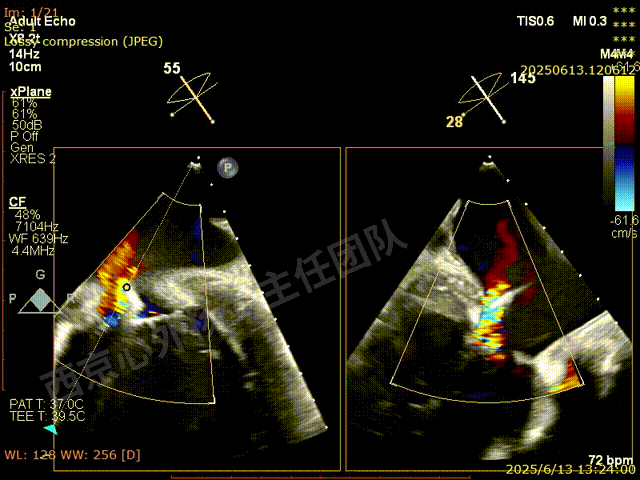

第一枚XTW释放后评估,外侧反流基本消失,内侧仍然有中度以上反流

第二枚XT于第一枚夹子内侧瓣上调整

第二枚XT关闭后评估,trace

二尖瓣平均跨瓣压差1mmHg

释放后评估,反流降至1+,组织桥稳定